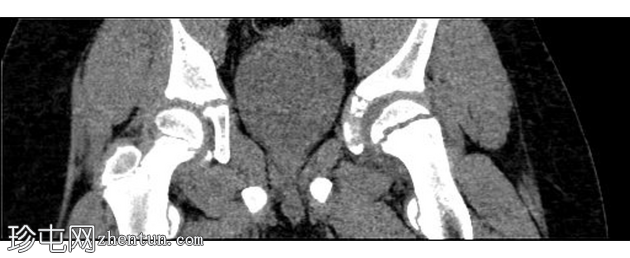

CT

冠状位

平扫

左侧股骨近端骨骺板增宽,伴有股骨近端骨骺向后内侧滑脱。影像学表现符合左侧股骨头骨骺滑脱。

急诊X线片显示可能存在股骨骨骺骨折,因此需要入院并进行皮肤牵引。入院后,CT扫描证实为左侧股骨股骨头骨骺滑脱。手术固定安排在次日进行。